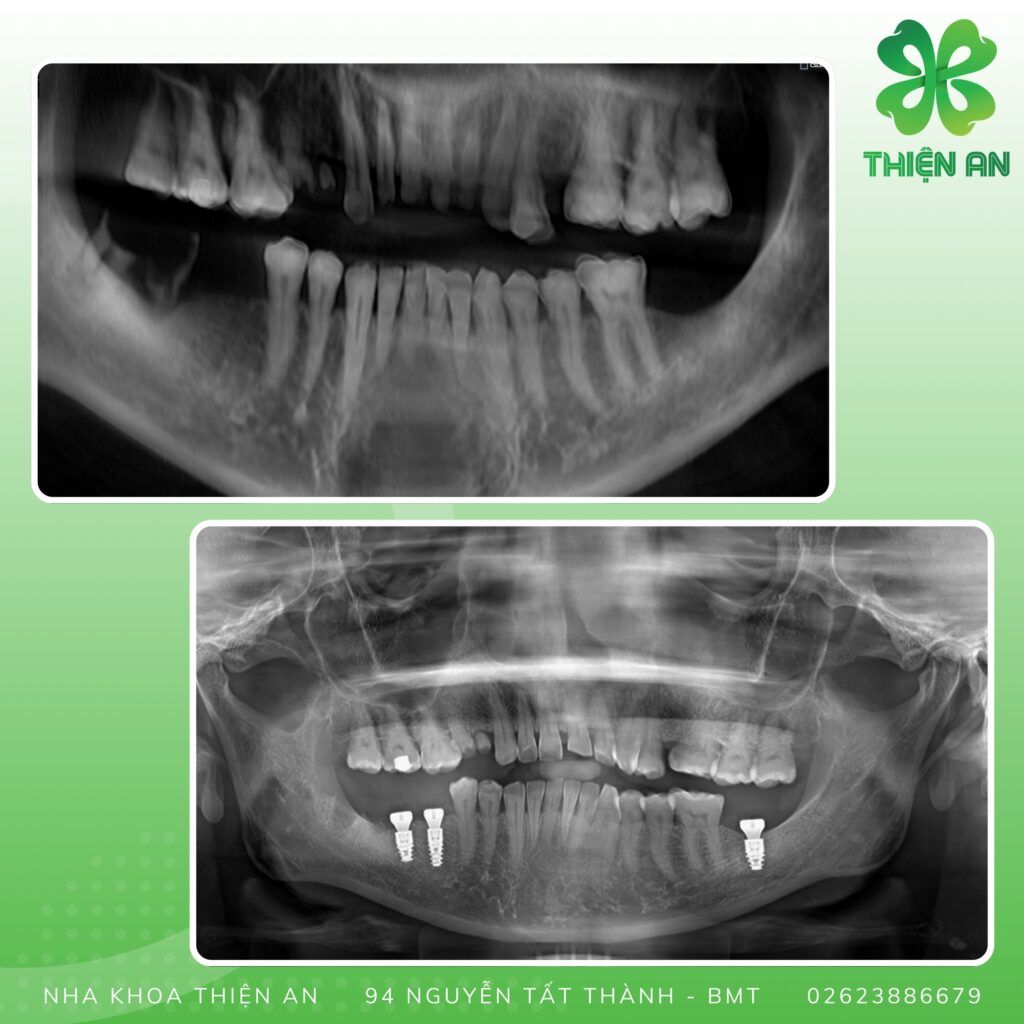

Cấy ghép Implant

Tiếp tục những ca cấy ghép Implant tại Nha khoa Thiện An BMT ĐăkLăk

Lựa chọn trụ Implant đúng và phù hợp trụ với từng tình trạng răng của khách hàng, sẽ đảm bảo cho quá trình phục hình diễn ra một cách suôn sẻ và nhanh chóng hơn.